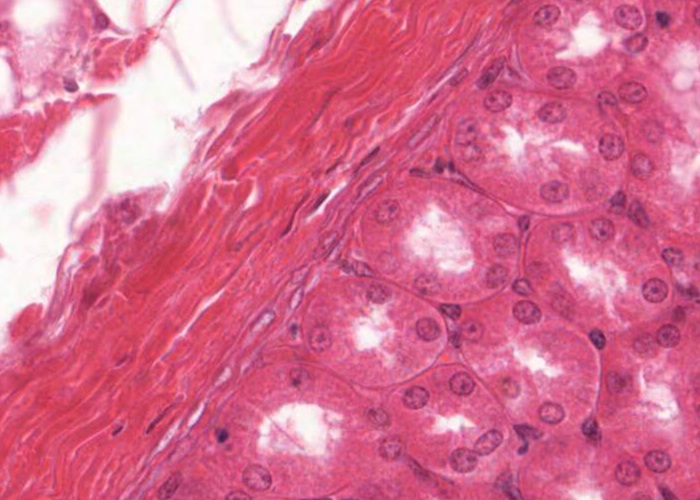

A renal corpuscle is located in the cortex and is the specialised structure where filtration occurs. Each is an aggregation of capillaries enclosed within a cup-shaped capsule called the glomerular (Bowman’s) capsule. Identify red blood cells within these capillaries. The capsule has an outer (parietal) surface layer of squamous epithelial cells and the inner (visceral) layer invests the glomerular capillaries.

The space between the glomerular capillaries and the parietal layer of Bowman’s capsule is referred to as the capsular or urinary space. This space receives plasma fluid that filters through the glomerular capillaries and the visceral layer of epithelial cells called podocytes.

In this H&E section, podocytes are difficult to distinguish from other populations of cells present (e.g. mesangial cells) but assume if you identify a cell nucleus on the periphery of the glomerulus that is larger and more spherical then it is probably a podocyte rather than a flattened nucleus belonging to an endothelial cell. You will see this distinction better when you view the renal corpscule where the basement membrane has been specifically stained and podocytes are definitely outside surface of the basement membrane of the capillary wall.